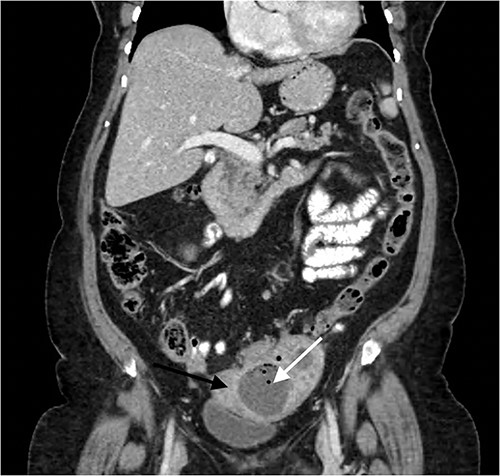

In 4 months, following an exacerbation of LIF pain, outpatient CT demonstrated the LIF mass had now progressed in size, up to 9.0 × 7.0 × 5.3 cm in dimension, with now multiple air fluid levels, accompanied with complete loss of the tissue planes between the lesion and the sigmoid colon. There was also free fluid in the Pouch of Douglas (POD), as seen in Fig. 3. As such, the conclusion was made that the patient had likely chronic Hinchey Class 2 diverticular abscess, requiring operative intervention.

Contrast enhanced coronal CT Abdomen/Pelvis revealing a larger multi-loculated rim enhancing LIF mass (white arrow) adherent to the uterus (black arrow), with air fluid levels and multiple locules of gas.